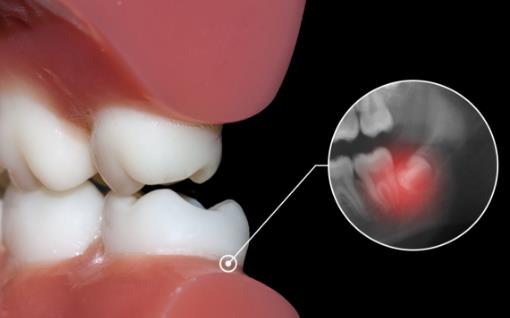

因为长智齿的年龄是18岁以后,牙齿的排列和结构已经形成,这个时候长智齿必须要破坏牙床或者破坏其他的牙齿,所以会非常的疼痛,但是疼痛有轻有重,如果长智齿的位置较好,不影响其他的牙齿,只是需要突破牙床就可以,那么这种智齿不会很痛苦,即使疼痛也可以忍受,对于这种智齿,做好必要的口腔护理,做到勤刷牙,就可以安然度过,等到智齿完全长出来,疼痛也就消失了。

智齿的位置不合适,很难长出来。如果智齿的位置不合适,需要对牙床或者其他牙齿进行破坏,那这个过程是非常痛苦的,而且,这种智齿也是很难长出来的,在长智齿的过程中因为破坏了牙床,很容易引起一些牙齿的炎症或者是牙周的炎症,甚至还可能引发高烧等症状。对于这种情况,一定要去医院进行治疗,消除炎症,缓解疼痛,等到智齿长出来之后立即进行拔除。

2.侵犯邻牙:通常患者不自知,而由牙医以X光诊断得知。通常智齿萌发的空间不足,而会倒在第二大臼齿上,因而造成第二大臼齿清洁不易,甚至是牙齿部分吸收的现象,造成患者不舒适或牙疼。

6.阻生齿:通常这是最讨厌的一种,牙医会觉得很难搞定,但病人却不一定有感觉,因此忽略了。这一种类型的牙齿,通常埋在齿槽骨的里面,如果会痛,或是诊断会有病灶发生的时候,就需要拔除了。